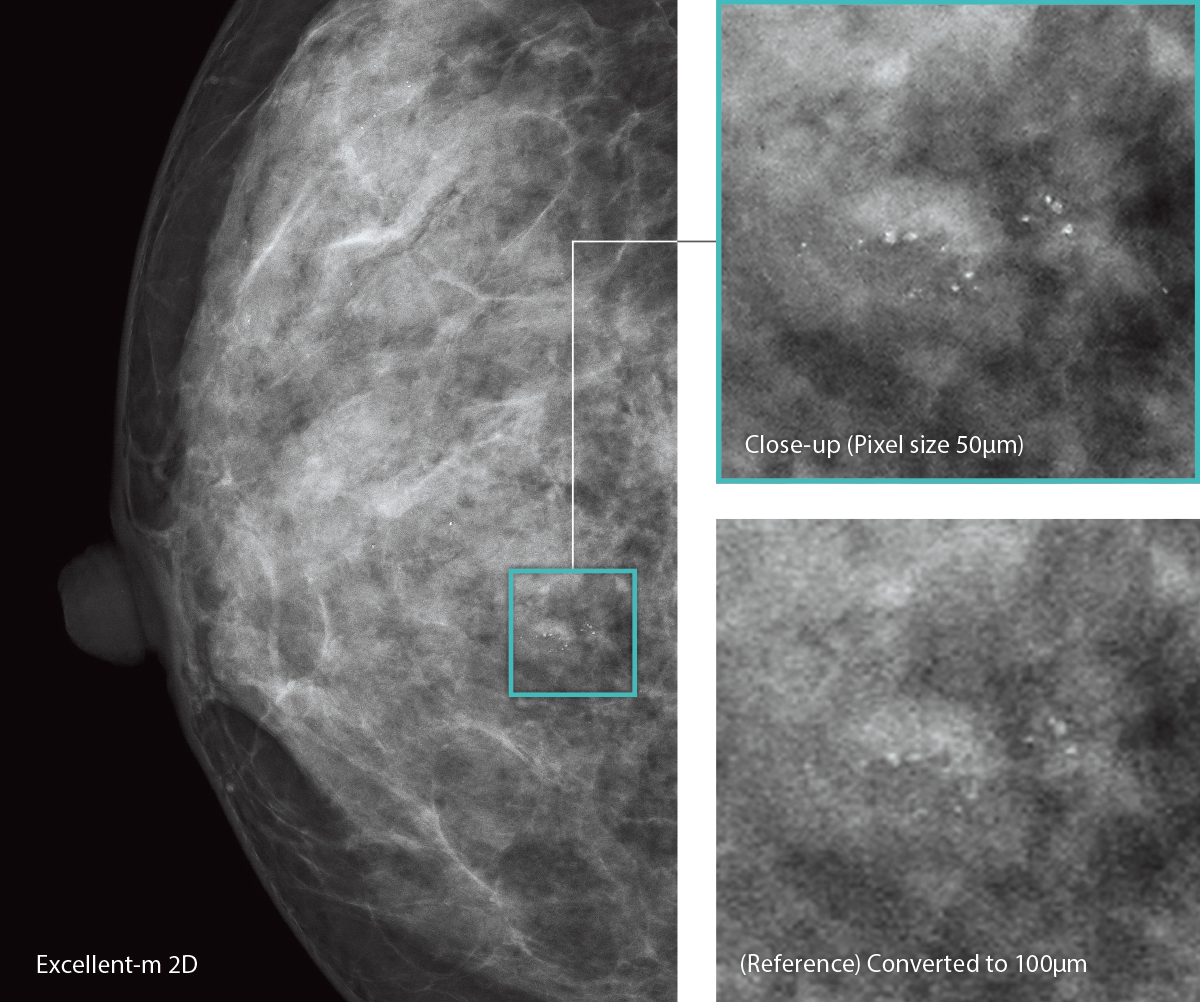

AMULET Innovality emplea un detector de panel plano de conversión directa compuesto por selenio amorfo (a-Se), que cuenta con una excelente eficiencia de conversión en el espectro de rayos X para mamografía. El detector de patrón hexagonal (Hexagonal Close Pattern, ECP) obtiene eficazmente las señales eléctricas convertidas de los rayos X para conseguir una alta resolución y un bajo nivel de ruido. Este diseño exclusivo permite obtener una mayor eficiencia cuántica de detección (Detective Quantum Efficiency, DQE) en comparación con el arreglo de píxeles cuadrados de los paneles TFT convencionales. Con la información recolectada por el detector HCP, AMULET Innovality crea imágenes de alta definición con un tamaño de píxel de 50 μm; el más fino disponible con un detector de conversión directa.